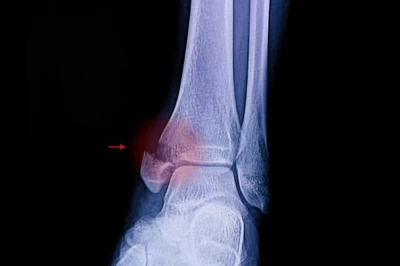

هشتگ درمان شکستگی مچ پا